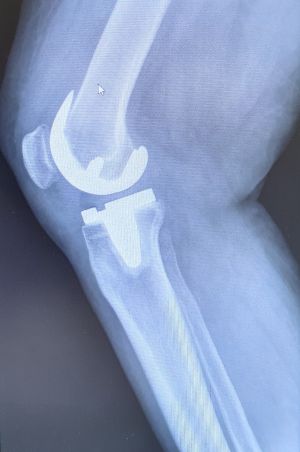

GONARTHROSE UND KNIEPROTHESE

Definition

Die Gonarthrose ist eine Abnützung des Knorpels im Kniegelenk. Dies kann posttraumatisch durch unfallbedingte Schädigung des Knorpels, als auch primär bedingt sein. Als prädisponierende Faktoren zählen dazu Übergewicht oder eine Achsfehlstellung (X- oder O-Bein).

Bei fortgeschrittener Arthrose des Kniegelenks und entsprechendem Leidensdruck ist der künstliche Kniegelenksersatz die Therapie der Wahl. Dabei werden zunächst die geschädigten Knorpelanteile schablonenhaft entfernt und die Gelenkflächen mit Metallflächen ersetzt. Diese Metallflächen artikulieren über einen Mittelteil aus hochvernetztem Kunststoff, dem sogenannten Inlay.